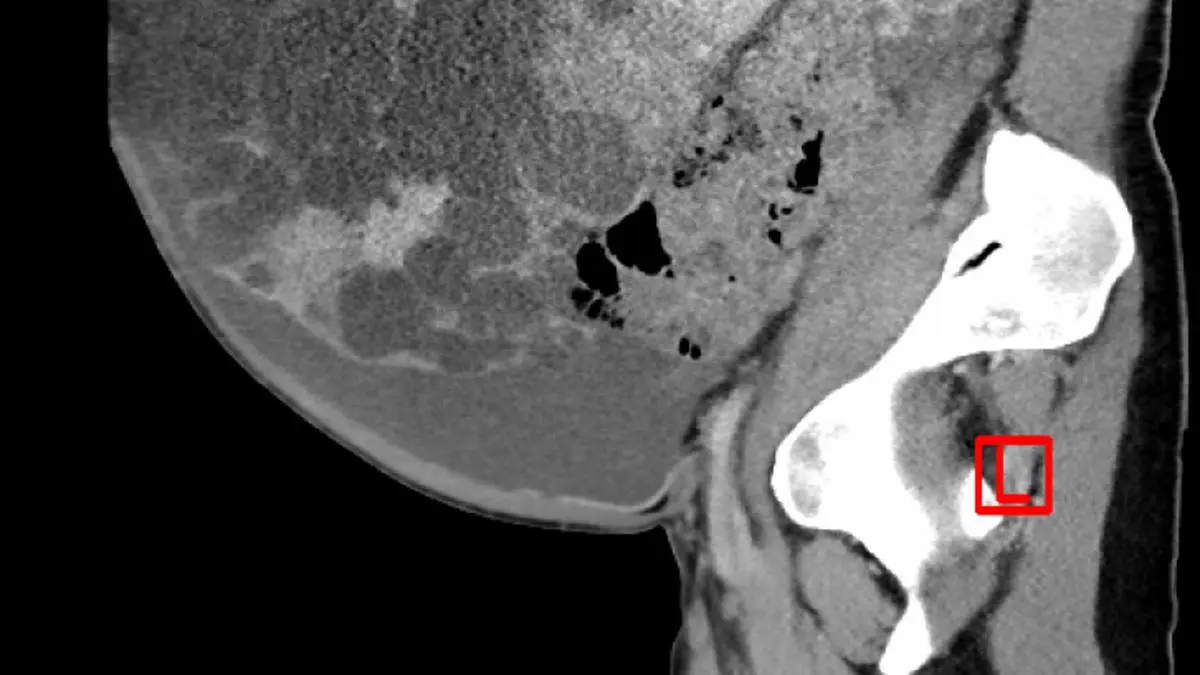

Ärzte entfernten Patientin 17,5 kg schwere Zystenleber

Eine fast 17,5 Kilogramm schwere Fehlbildung der Leber haben Mediziner am LKH-Uniklinikum Graz einer Patientin entfernt. Die von Zysten durchsetzte Leber hatte große Teile des Bauchraums ausgefüllt und auch extrem viel Wasser angesammelt. Das Organ musste vollständig transplantiert werden. Die 34-Jährige Patientin zeigte sich sechs Monate nach dem Eingriff beim Pressegespräch in Graz erleichtert.